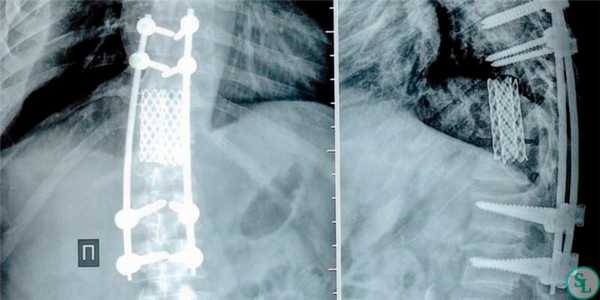

Оперативное вмешательство проводится при неэффективности консервативной терапии, выраженной нестабильности позвоночника, тяжелом неврологическом дефиците. Показаниями к операции служат признаки эпидурита, свищей, угроза сепсиса. При некупируемом болевом синдроме рассматривается возможность нейрохирургического вмешательства. Операции при спондилодисците направлены на ликвидацию очага инфекции, стабилизацию костных структур.

Целями оперативного вмешательства являются ликвидация инфекционного очага, взятие биопсии для микробиологического и гистологического исследования, декомпрессия позвоночного канала со стабилизацией и восстановлением поврежденных спинальных структур

Дискэктомия (удаление разрушенного диска) и корпэктомия (удаление фрагмента тела позвонка) позволяют полностью очистить пораженные ткани. Внедрение распорочных трансплантатов (вырезанных из костных структур, взятых в ребрах или гребне подвздошной кости) позволяет хрящевым тканям начать восстанавливаться, а фиксирующие позвоночный столб титановые конструкции временно снимут нагрузку на пострадавшие позвонки. Реабилитация занимает от 3 месяцев до полугода.

Двухэтапное вмешательство предпочтительно у пациентов без неврологического дефицита, но имеющих сопутствующую патологию. Второй этап операции проводится спустя одну или две недели после первого [5]. Вид оперативного вмешательства зависит от уровня поражения, степени деструкции и развившихся осложнений. При этом на первом этапе операции производится удаление пораженных и некротизированных тканей посредством корпоротрансверзэктомии, дискэктомии или ламинэктомии.

На втором этапе осуществляется восстановление опорной и защитной функций позвоночника По истечении времени иммобилизации пациенту назначается физиолечение, УЗТ, иглорефлексотерапия, ЛФК. Длительное ограничение двигательной активности приводит к атрофии мышц, возвращение к нормальной жизни проводится постепенно с увеличением объемом нагрузки и движений .